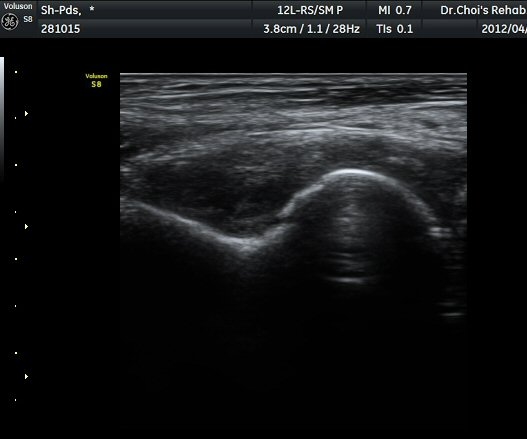

ÆÈ²ÞÄ¡ ÁÖµÎ¿Í Á¾´Ü¸é°Ë»ç À§Ä¡¿¡¼­ ŽÃÊÀÚ ¿ÜÃøÀ¸·Î ÁÖ»ç¹Ù´ÃÀ» »ðÀÔÇÏ¿©

°üÀý³» ÁÖ»çÄ¡·á ½ÃÇà(ÁÖ»ç »çÁø). °üÀý ³» ÁÖ»ç¾×ÀÌ µé¾î°¡´Â °ÍÀÌ ¶Ñ·ÈÈ÷

°üÂûµÇ¾î Áֻ簡 Àß µÇ¾úÀ½À» È®ÀÎÇÒ ¼ö ÀÖ´Ù(ÁÖ»ç µ¿¿µ»ó) .